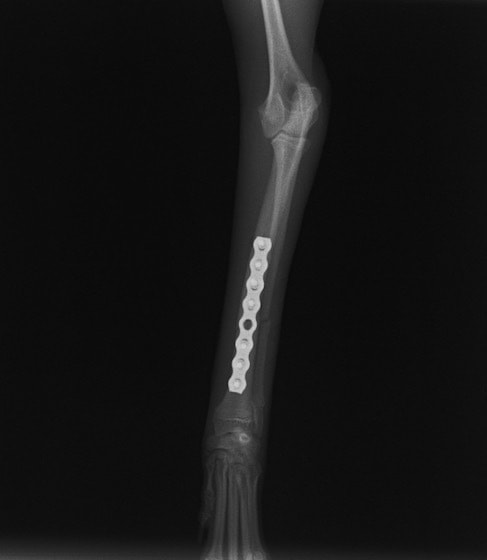

トイプードル 右遠位橈尺骨短斜骨折のALPSによる内固定

Locking Compression Plate

LCPは、スクリュー(ネジ)とプレート(金属の板)をロックする特殊な構造により骨折部位を固定する新しい世代のプレートシステムです。ひとつのホールでロッキングスクリューとスタンダードスクリューの使用を選択できるユニークな構造をしているため、骨折断端間の圧迫を目的とした従来型プレート固定法に加え、高い角度安定性を有するロッキングスクリューを用いた固定法の選択が可能です。従来のプレートシステムでは困難だった部分の骨折や癒合不全の症例に高い治療効果をもたらします。